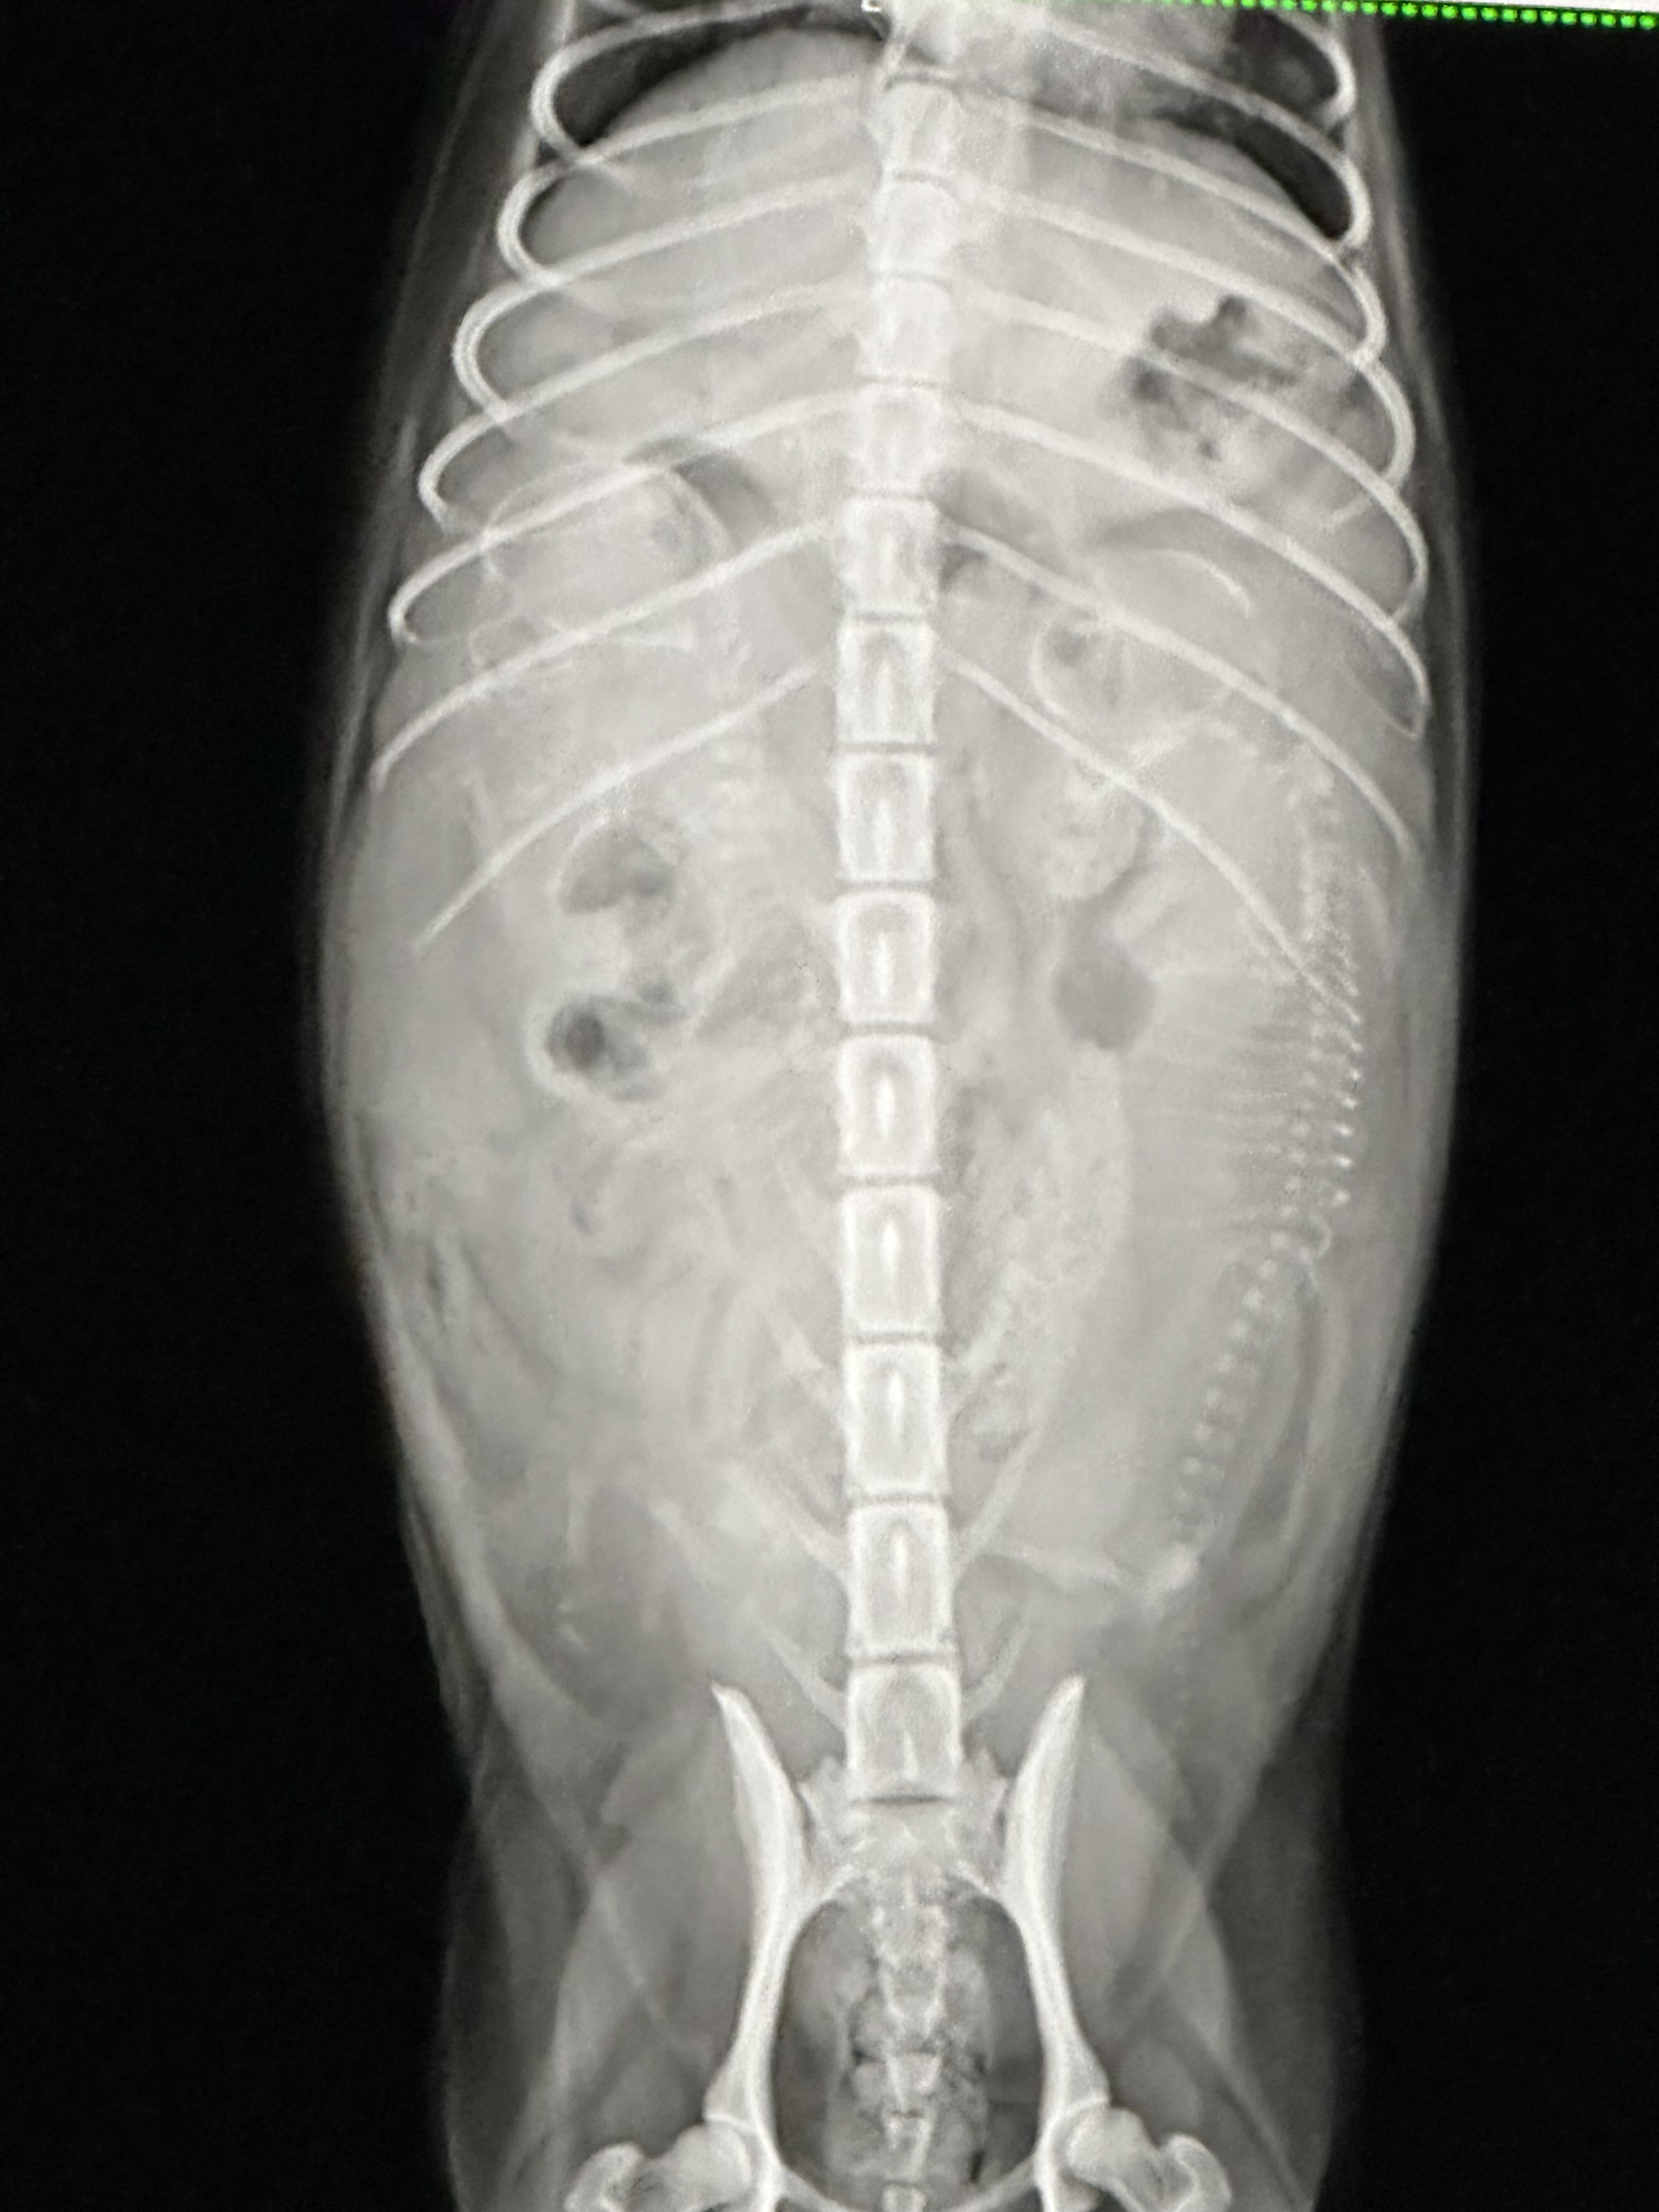

レントゲン

いよいよ、お腹も大きくなったホワイトの母犬「立花」のレントゲン検査に行ってまいりました。

出産頭数も確定し、いよいよ数日以内に出産を迎える予定です。

これまでで最も多い頭数となりそうですが、その分一頭一頭は小さめに生まれる見込みで、現時点では落ち着いて見守っております。